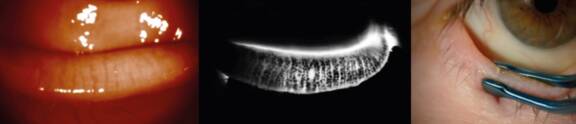

Le docteur Serge Doan nous dévoilera ses secrets d’expert pour examiner « vite et bien » l’état de nos précieuses glandes meibomiennes. Cet examen de routine, trop souvent négligé, permet d’avoir une meilleure efficacité dans la prévention des signes fonctionnels de l’œil sec.